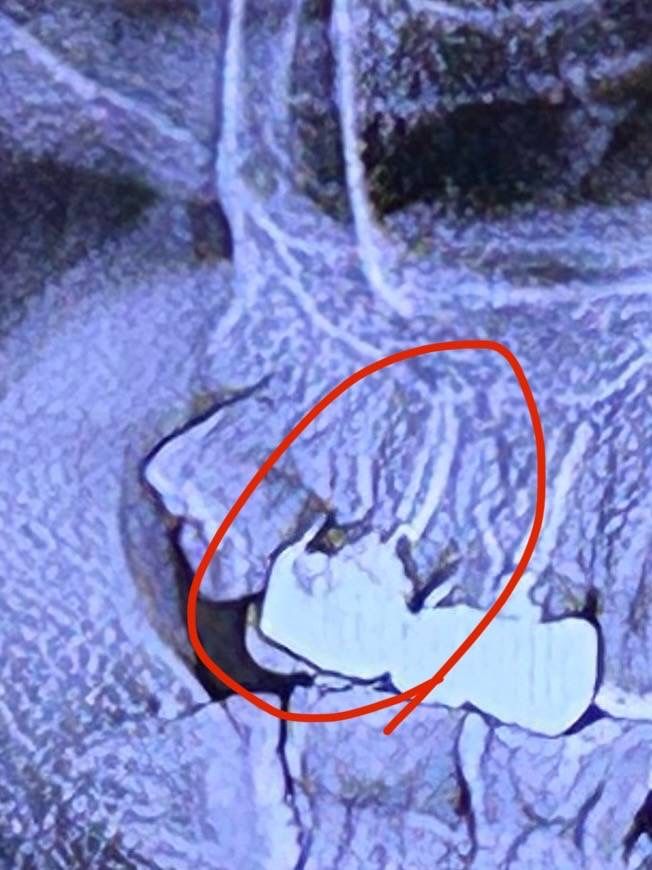

24년 6월에 신경치료를 받고 11월에 타 사랑니 치과에서 충치 소견이 보인다해서 기존 치료를 받았던 치과에 내원해서 물어보니 문제가 없다 하셨습니다.

근데 아무리봐도 내부에 심한 충치가 의심돼서 다른 병원에서 크라운을 까고 확인했을때 안쪽에 충치가 심하게 진행되어 있으면 처음 치료한 병원에 보상 받을 수 있을까요..

이 사진은 24년 11월 사진입니다..

• 1번 째 사진